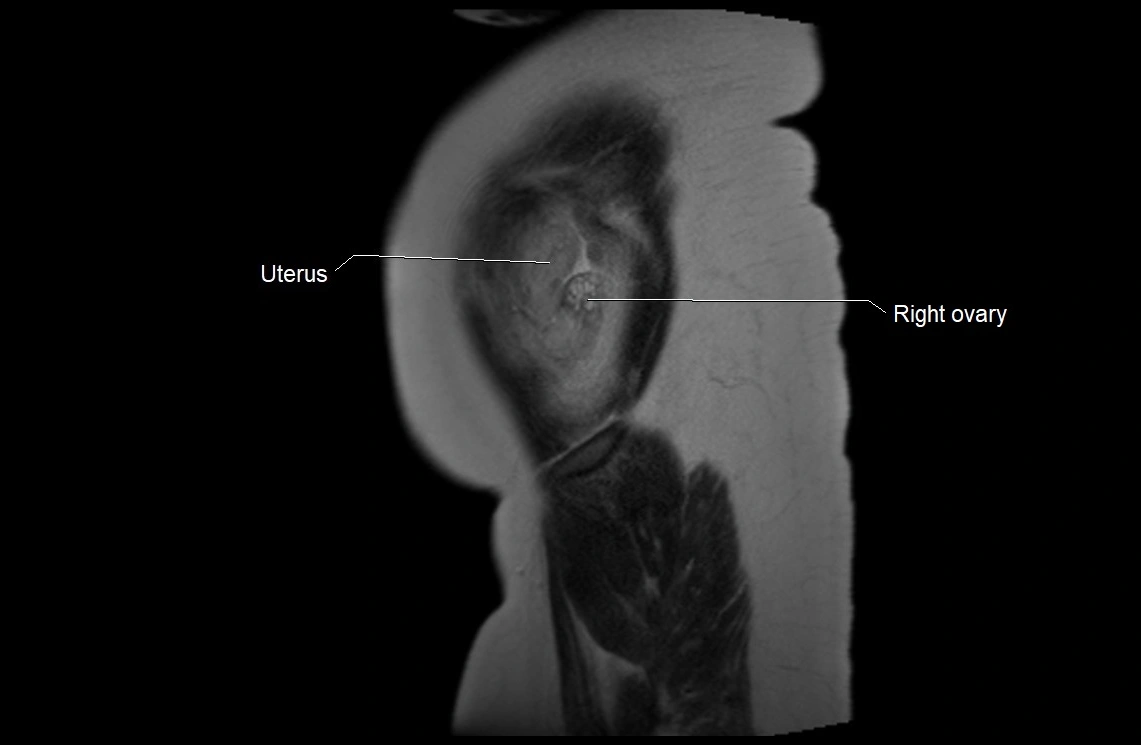

Relations

• Enclosed within the amniotic sac, bounded by the amnion and chorion

• Surrounds and cushions the developing fetus

• In continuity with maternal circulation through placental and transmembrane exchanges